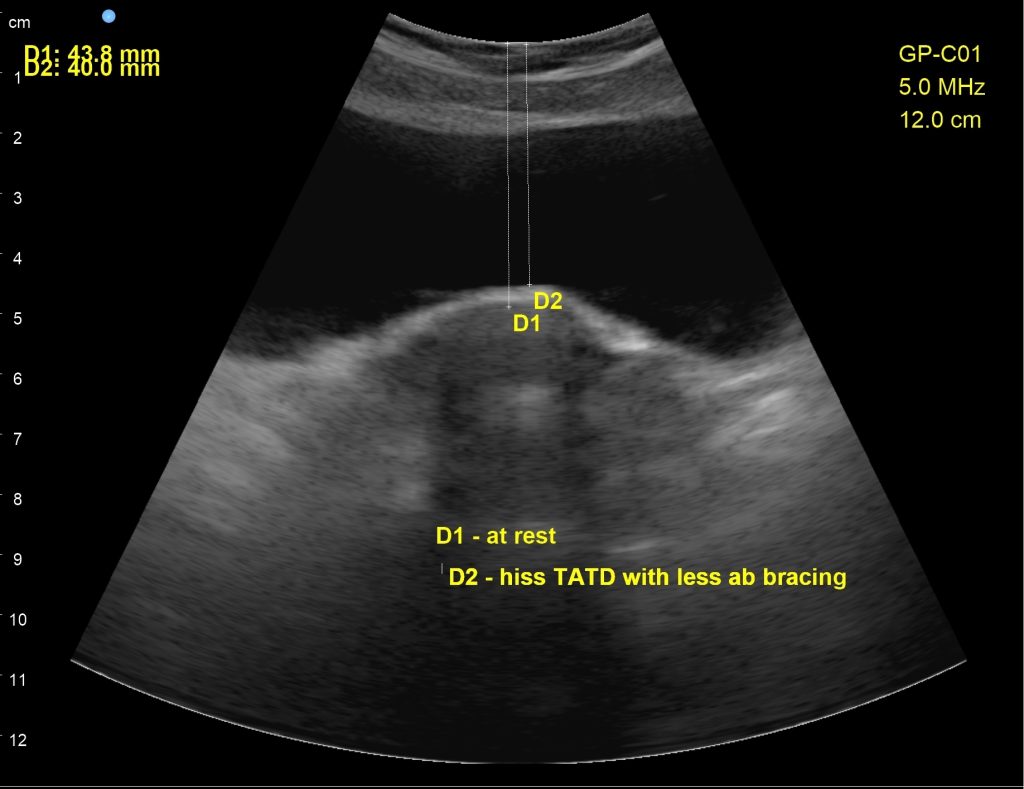

In the second scan, I used a subphonation “hiss” sound, or what I call a “top down” cue in order to lessen the rigid holding of the abdominals, which then put less pressure downward through the pelvic floor. Using regular cues for ab strengthening, the patient was putting too much downward pressure on the pelvic floor, causing leakage. This cue helped her stop leakage and return to running.